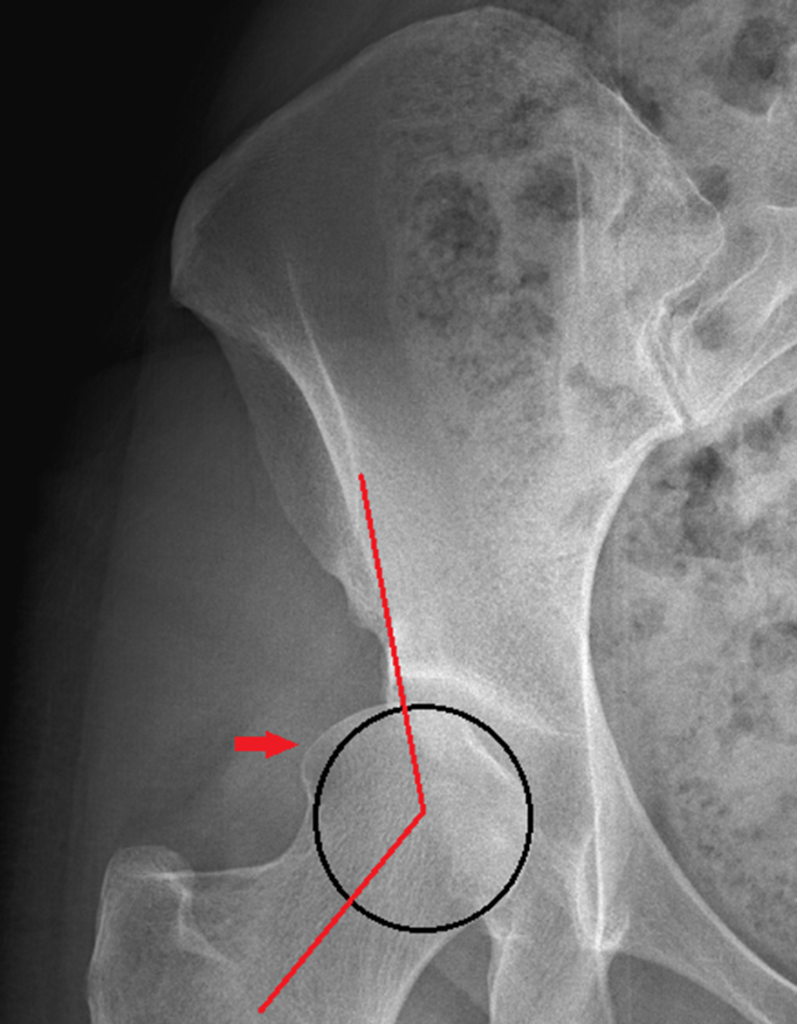

Tonnis Angle

The Tonnis angle measures the upward slope of the hip socket. A slope between 0-10 degrees is normal and allows for even loading across the joint.

>10 degrees: a steep slope may be seen with dysplasia. This increases load/stress placed across smaller parts of the joint, and can cause pain and damage to the cartilage.

< 0 degrees: a shallow slope may be seen with FAI. This can cause pain and may limit hip range of motion.

– A slope between 0-10 degrees is normal and allows for even loading across the joint.